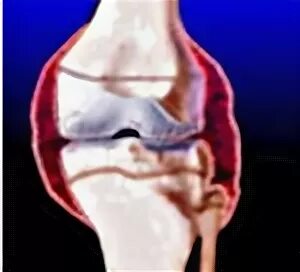

Минимально выраженный синовит